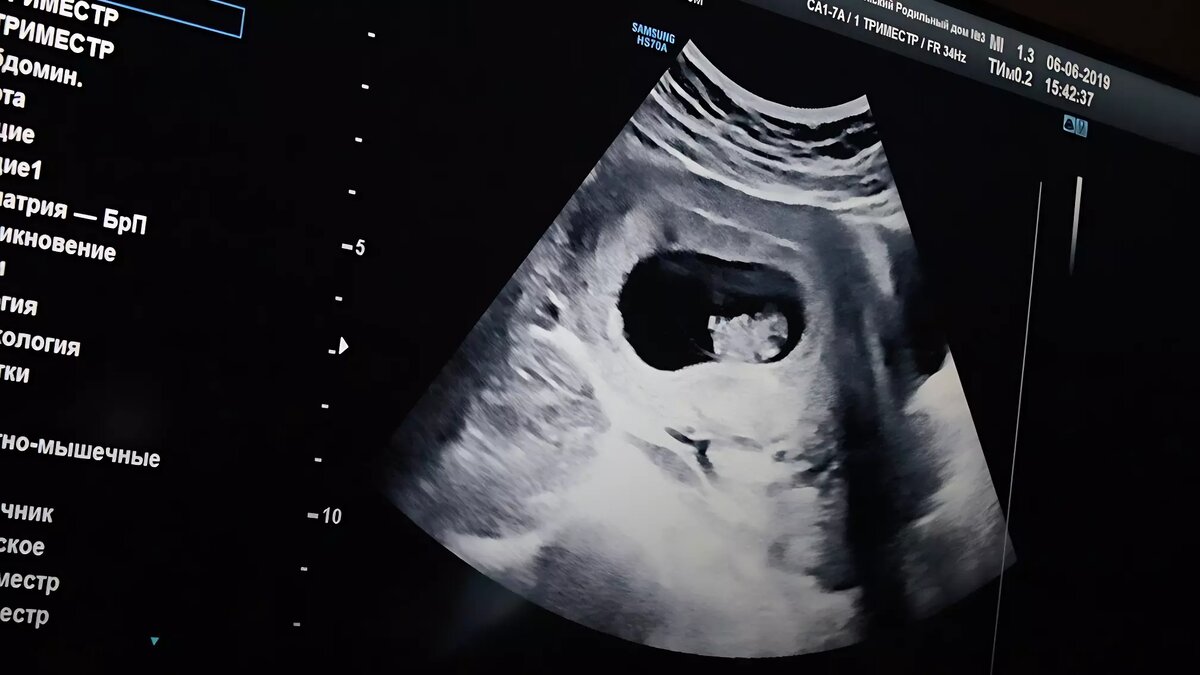

В Тюменской области 154 женщины сделали аборт после того, как у плода были выявлены патологии в развитии. Об этом сообщает Ura.ru со ссылкой на доклад властей.

За 2023 год перинатальную диагностику аномалий развития плода прошли 14 692 тюменки на сроке до 14 недель беременности, что составило 94% от взятых на учет на данном сроке. В результате диагностики у 74 плодов выявили хромосомные патологии, еще у 408 — анатомические дефекты.

В прошлом году в Тюменской области родились два ребенка с особенностями. У одного отсутствовала кисть руки, у другого — почка. Иногда такие патологии нельзя зафиксировать даже во время УЗИ.